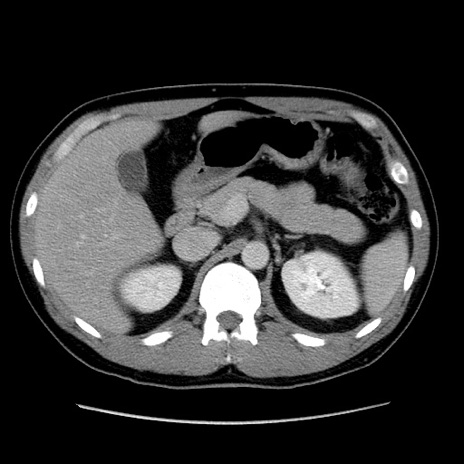

冠状断像

【症例】30歳代男性

【主訴】腹痛、嘔吐

【現病歴】昨晩から突然の腹痛あり、その後嘔吐、軟便も出現。腹痛が改善しないため救急搬送となる。2日前にしめ鯖の食事歴あり。

【身体所見】意識清明、苦悶様、BP 135/90mmHg、BT 35.7℃、腹部:平坦、やや硬、心窩部〜臍部に自発痛、圧痛あり、筋性防御+、反跳痛-

【データ】WBC 8100、CRP 0.57